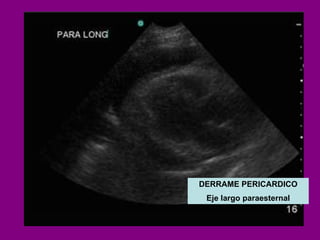

DERRAME PERICARDICO

DERRAME PERICARDICO Eje largo paraesternal